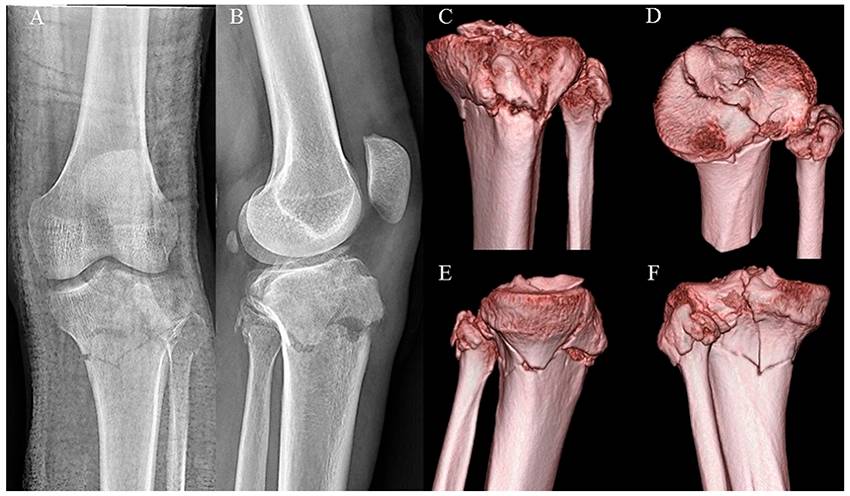

Open tibial plateau fractures: Infection rate and functional outcomes

Complications and timing of soft tissue coverage after complete articular, open tibial plateau fractures